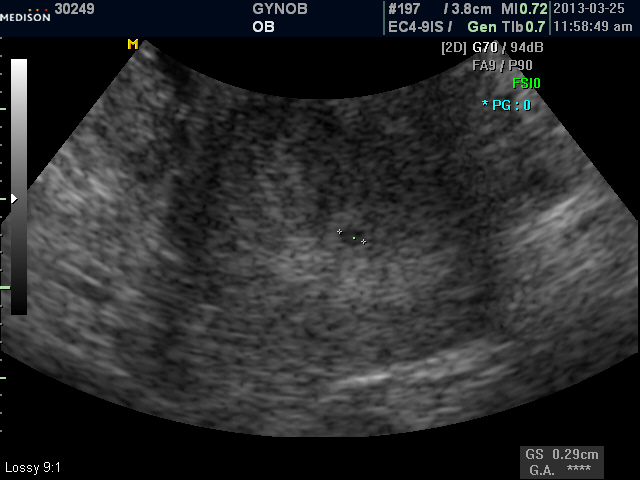

ksy.JPG (95.97 KB, 다운수: 583)

스마트폰 모드|진오비 산부인과